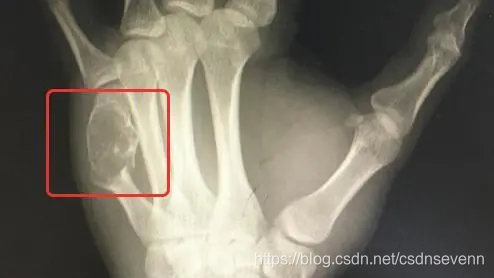

“这可不是‘一般的键盘手’,你左手这根骨头里的东西,其实是内生性软骨瘤,它把你正常的骨头都‘融’成‘豆腐渣’了,所以骨头才会一碰就裂开了。需要刮除肿瘤组织同时固定骨折的掌骨。”医生解释道。

图源:钱江晚报

据悉,内生性软骨瘤是一种发生于骨内的良性骨肿瘤,一般没有症状或伴有轻微酸痛、无痛性肿胀,看起来更像肢体的局部肿胀,并且其生长速度缓慢,数年内体积也无明显变化,所以多数病人是出现了病理性骨折后才被检查出此病。